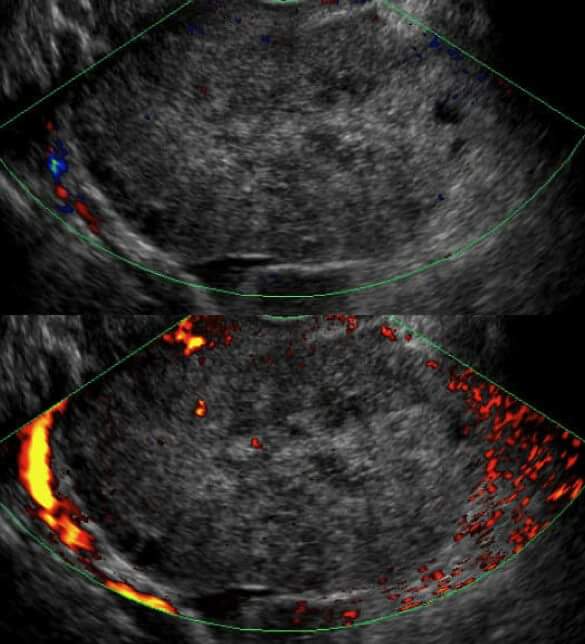

Sonographic findings

- Unilaterally enlarged ovary

- Peripherally displaced follicles due to edema

- Coexistent mass

- Twisted pedicle (not always seen)

- Free fluid

Doppler

- little or no intra-ovarian venous flow

- absent arterial flow (poor prognostic sign)

1 yo female with right ovarian torsion